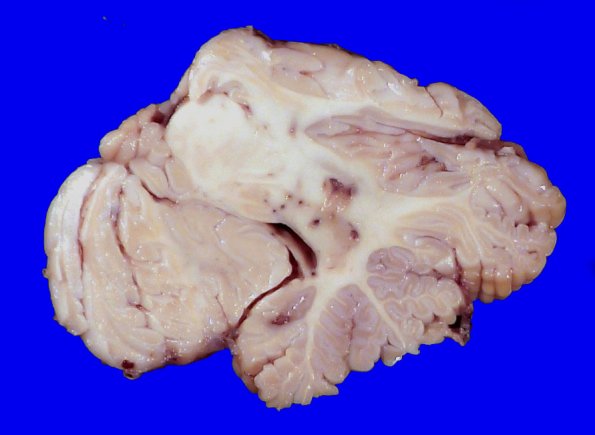

23F5 Infarct tumor embolus (Case 23) 1_6

Lesions are not confined to the cerebral hemispheres, seen here in the cerebellar dentate nucleus.